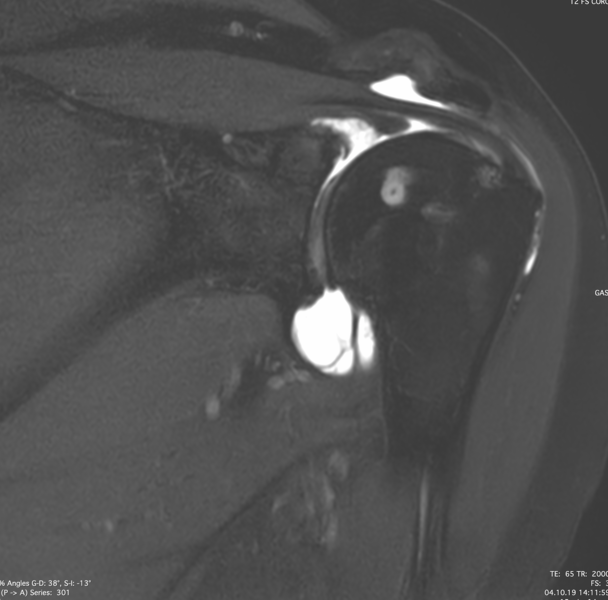

Articular-side tears